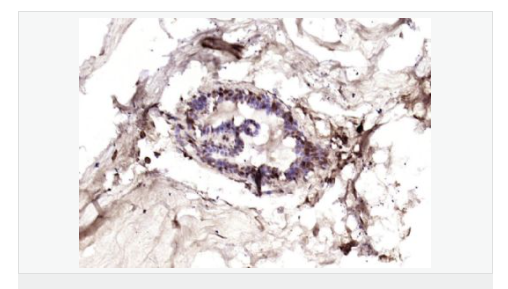

交叉反應:Human(predicted:Mouse,Rat) 推薦應用:IHC-P,IHC-F,IF,ELISA

| 產(chǎn)品應用 | ELISA=1:5000-10000 IHC-P=1:100-500 IHC-F=1:100-500 IF=1:100-500 (石蠟切片需做抗原修復) not yet tested in other applications. optimal dilutions/concentrations should be determined by the end user. |